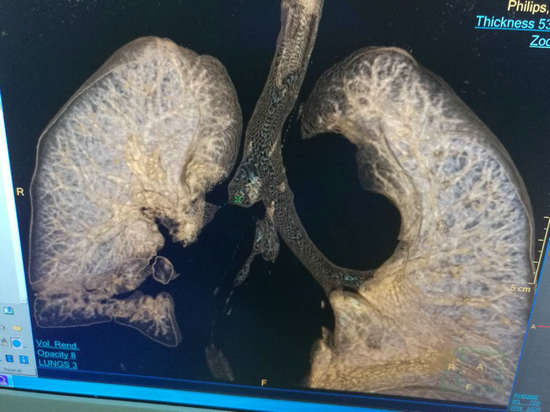

正所谓天无绝人之路,通过亲戚朋友介绍,霍先生的妻子打听到郑州大学五附院心胸外科对处理危重胸外伤有丰富的经验,便抱着试一试的态度连夜转到郑州大学五附院。住院后在高兴才主任指导下,患者的病情一度得到控制,入院后的一周后患者多次突然出现胸闷、气促、呼吸困难,心电监护示:心率110次/分,氧饱和60%左右。值班医师陈涛马上安排急诊床旁胸片检查,结果显示:右肺未见肺纹理(图一),出现了临床上可怕的“大白肺”,在与冯光强副主任医师商议后,考虑患者痰栓阻塞气管引起右肺实变,病情危重。与患者家属沟通后,把霍先生转入呼吸重症监护室,予以气管插管,同时呼吸机辅助正压通气,待情况稳定后行气管镜发现,右主支气管狭窄,气管镜不能通过。复查胸部CT(图二)也证实了气管狭窄的存在。

▲ 图二(箭头所示为气管狭窄)

▲ 为了了解气管狭窄长度,制定手术方案,高兴才主任医师带着患者做了气管重建检查

由于手术难度大,术中不可预知情况多,经过术前讨论高兴才主任认为,患者右主支气管狭窄长度约1-2cm,可实施“支气管成形术”,虽然有术中切除肺叶的可能,但患者比较年轻,应尽最大可能保留右肺上叶。经过积极术前心肺功能准备后,于7月16日,高兴才主任医师、冯光强副主任医师在麻醉科胡强夫主任及其团队的配合下,全麻双腔插管给霍先生实施了“右主支气管成形术”。打开胸腔后发现,胸腔广泛粘连,而且因为炎症的原因,患者组织脆、水肿,解剖发育异常,都给手术增加了难度。但是,为了保留患者右上肺,术者仔细操作,认真分离,终于完整切除了狭窄的气管,同时成功吻合断端,术中患者顺利脱机后返回病房。